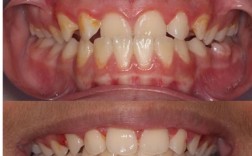

隐形正畸作为一种美观、便捷的牙齿矫正方式,已被广泛接受,但部分患者在矫正过程中可能出现牙根吸收问题,牙根吸收是指牙根表面牙骨质的病理性吸收,导致牙根长度变短,严重时可能影响牙齿稳固性和使用寿命,了解隐形正畸中牙根吸收的原因、影响因素及应对措施,对保障矫正效果至关重要。

牙根吸收在正畸治疗中并非罕见现象,数据显示传统正畸中牙根吸收发生率约20%-30%,而隐形正畸因材料特性与施力方式,其发生率与传统矫治相近,但影响因素存在一定差异,隐形正畸通过一系列透明牙套施加持续轻力移动牙齿,若力学设计不当或患者个体条件特殊,可能诱发牙根吸收,其发生机制主要与以下因素相关:一是力学因素,牙套施加的力值过大、作用点偏移或持续时间过长,会超过牙根牙周组织的生理耐受阈值,导致破骨细胞活性异常,引发牙根吸收;二是个体差异,部分患者存在遗传性易感性,如牙根发育较短、牙骨质厚度不足,或伴有系统性疾病(如甲状旁腺功能亢进),可能增加吸收风险;三是矫治设计问题,如附件位置偏差导致牙冠移动方向异常,牙根受到非生理性侧向力,或牙齿移动距离过大、速度过快,超出牙周组织改建能力;四是患者依从性,若未按时更换牙套、频繁摘戴导致矫治力中断或累积,也可能影响牙根健康。